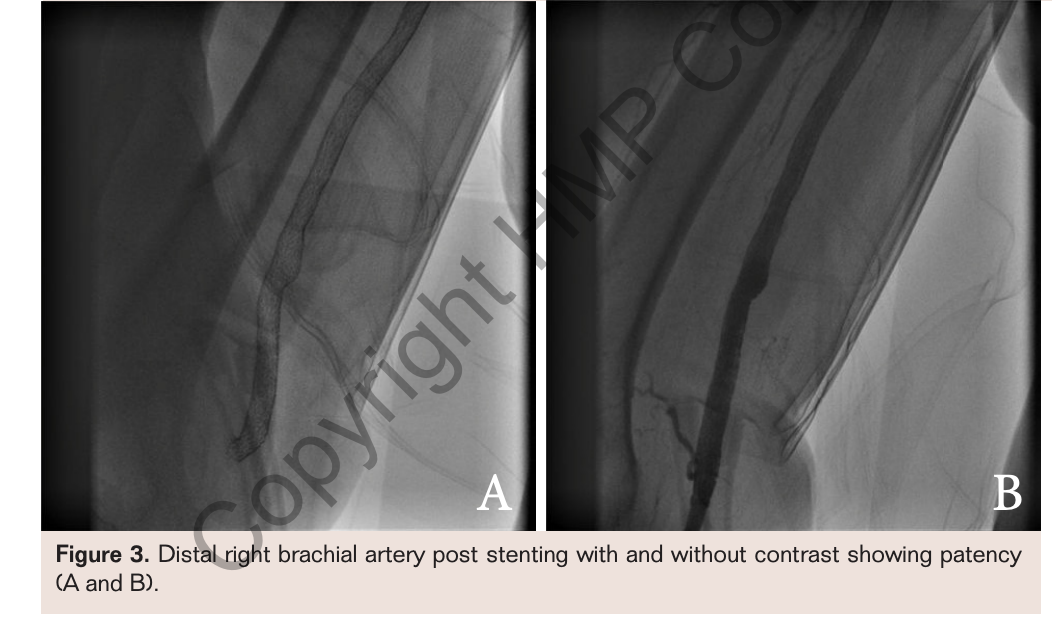

A more proximal 8 mm x 80 mm LifeStent FlexStar XL was deployed and then post dilated with the Fox Plus 6 mm x 120 mm PTA catheter. Final angiograms revealed a widely patent lumen. Post intervention examination revealed that the right brachial, radial, and ulnar pulses were restored: 2+ brachial, 1+ radial, and trace ulnar. An upper extremity ultrasound of this patient at 6-month follow-up and 18-month follow-up was consistent with healthy flow in her right brachial, radial, and ulnar arteries with continued stent patency (Figures 2 and 3).